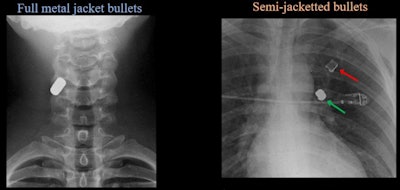

Several images illustrated the difference in impact between full metal jacket bullets versus semi-jacketed bullets.

(Left) AP radiograph of cervical spine demonstrates single-density well-defined bullet within right posterolateral soft tissues of neck at C4 level, consistent with full metal jacket bullet (Right) Two different densities of ballistic material. Lower-density fragment in left upper lobe is copper jacket and high-density metal fragment is lead core, consistent with semi-jacketed bullet. Images courtesy of the ARRS.

(Left) AP radiograph of cervical spine demonstrates single-density well-defined bullet within right posterolateral soft tissues of neck at C4 level, consistent with full metal jacket bullet (Right) Two different densities of ballistic material. Lower-density fragment in left upper lobe is copper jacket and high-density metal fragment is lead core, consistent with semi-jacketed bullet. Images courtesy of the ARRS."When interpreting imaging, one should use a mechanistic approach to establish bullet trajectory followed by assessment for injuries along the established path. Retained bullet fragments should be considered MRI conditional, and with the appropriate preceding workup patients, may be safely imaged,"